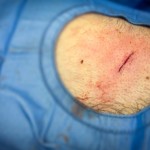

Attraverso le varie tecniche di esecuzione delle biopsie incisionali viene in ausilio alla clinica ed agli strumenti di secondo livello per permettere l’esecuzione di un esame istologico sul tessuto prelevato.

Secondariamente costituisce il principale cardine terapeutico per i tumori cutanei, purtroppo estremamente frequenti e spesso localizzati ad aree di elevato interesse estetico come il volto.

La chiusura della breccia chirurgica può avvenire per prima intenzione, seconda intenzione o attraverso l’impiego di tecniche più complesse quali lembi o innesti. Questo dipende da molteplici fattori come sede e dimensioni del difetto, morbilità, causa del difetto, anamnesi e volontà del paziente.

le cisti sebacee colpiscono molto frequentemente la sede periauricolare. Talvolta si formano a causa dell’occlusione dello sbocco di una ghiandola. La situazione che lei descrive, caratterizzata da aumento di dimensione, arrossamento, e dolore sembra una cisti “infiammata”: a volte la situazione rientra ( ovvero riduce la cisti senza farla sparire) con una terapia antibiotica locale, talvolta è necessaria una terapia sistemica. Sconsiglio di eseguire manovre fai da te di svuotamento della cisti che potrebbero infettarla. Si immagini la cisti come un palloncino: le cellule costituiscono la parete e producono il sebo che riempie il palloncino. Anche svuotando la cisti, la capsula riformerà il sebo con il tempo. La soluzione definitiva è di solito rappresentata da un piccolo intervento chirurgico per asportarla in toto. È meglio eseguirlo, quando possibile, senza che la cisti sia infiammata.